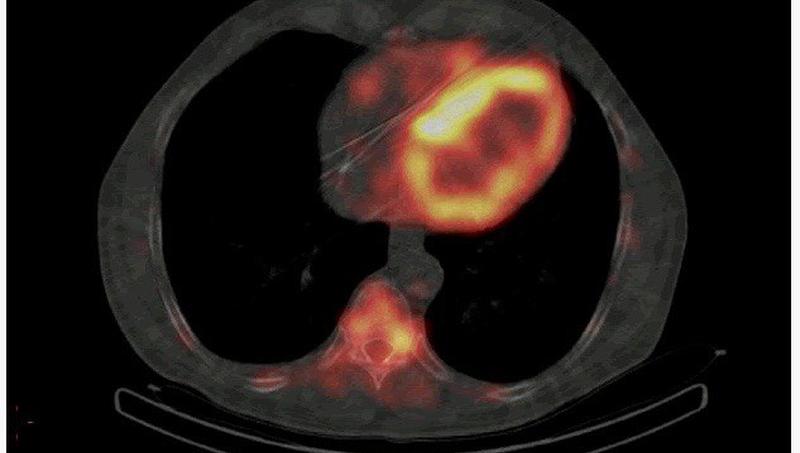

12 мая — особый день в истории Центрального военного клинического госпиталя имени А.А. Вишневского. В этот день 1981 года здесь была выполнена первая операция АКШ (аорто-коронарное шунтирование). Операции на открытом сердце стали возможными в ЦВКГ спустя почти 20 лет после первых таких операций в мировой врачебной практике. Тогда это были единичные АКШ в нашей стране. Сегодня в 3 ЦВКГ на открытом сердце делают около 1 500 операций в год.

Два десятилетия назад в 3 ЦВКГ имени А.А. Вишневского Министерства обороны РФ образован кардиохирургический центр. За 20 лет он превратился в своего рода визитную карточку госпиталя и занимает лидирующее положение в системе оказания современной, высокотехнологичной медицинской помощи не только в вооружённых силах, но и в целом в стране. Об истории создания, развития и сегодняшнем дне кардиохирургического центра рассказывает его начальник, заслуженный врач РФ, доктор медицинских наук, профессор, полковник медицинской службы Александр Лищук.